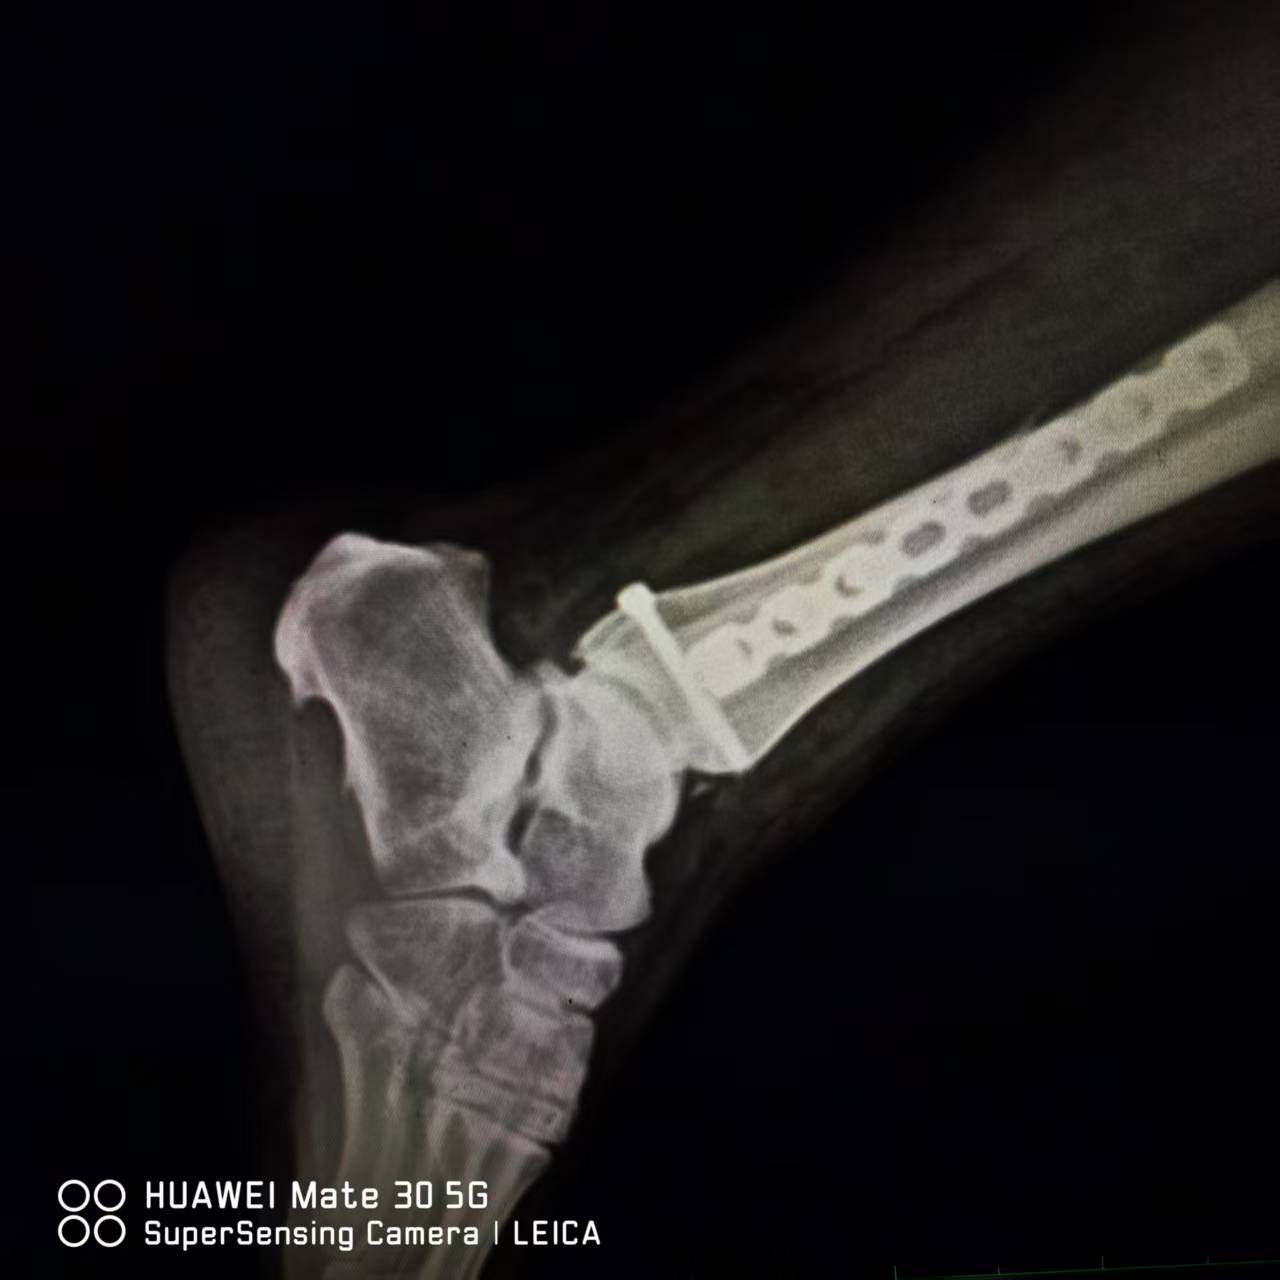

8月14日上午,董庆武主任带领骨科团队,在全麻麻醉下,为患者行右外踝切开复位锁定钛板螺钉内固定,后踝切开复位拉力螺钉内固定,术中,专家团队凭借精湛医术和丰富经验,精准地对骨折部位进行复位和固定,术后摄片效果满意。